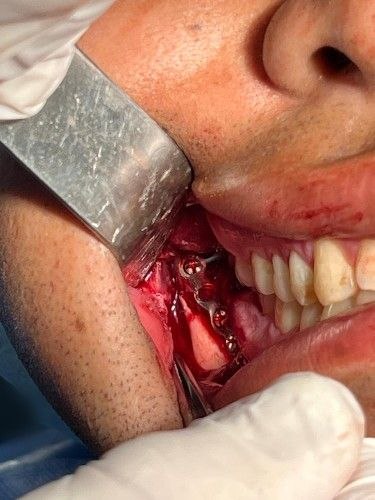

Aplicamos la técnica intrabucal de reducción de fractura sin cicatrices, logrando resultados funcionales y estéticos óptimos para nuestros pacientes.